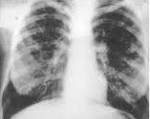

J84.1 Другие интерстициальные легочные болезни с упоминанием о фиброзе